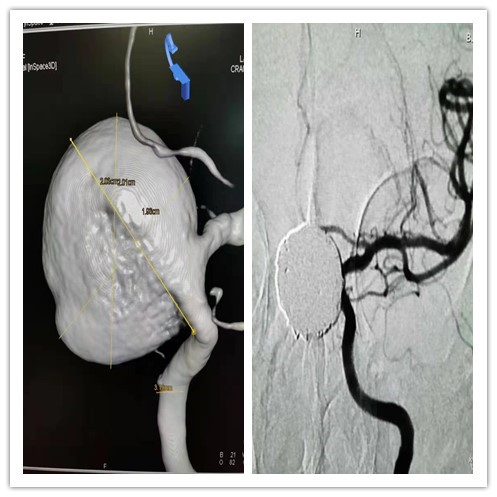

近日,一位患巨大脑动脉瘤、辗转多地求医的女性患者,向首都医科大学附属北京天坛医院神经介入中心求助,此时患者已经出现剧烈头痛、血压不稳情况,动脉瘤随时可能破裂危及生命。北京天坛医院刘爱华团队迅速制定“双保险”手术方案,最短时间内“拆除”了患者颅内超过2厘米的“定时炸弹”。

“这么大的动脉瘤,一旦发生破裂,几分钟内就可能导致患者死亡,抢救的机会都没有。”北京天坛医院神经介入中心主任医师刘爱华介绍,患者的动脉瘤超过2厘米,已经到了生死“临界线”,必须及时进行积极治疗。

患者动脉瘤巨大,且生长于眼动脉,给手术操作带来极大难度。“动脉瘤附近的血管有些扭曲,对于手术操作来说有些麻烦;血管壁非常薄,术中操作填塞弹簧圈的时候可能会导致破裂出血。”此外,由于介入手术后大概需要3-5天甚至更长时间才能显现出效果,在此期间动脉瘤仍有破裂的风险。

针对这种情况,北京天坛医院神经介入中心、神经外科和神经内科专家多次进行会诊、评估,最终同意了刘爱华团队提出的“密网支架结合弹簧圈致密填塞”的“双保险方案”。

“密网支架是目前最先进的技术,使血流减少通过,减少动脉瘤远期复发和破裂的风险;使用最大的弹簧圈进行填塞,能够预防即时的出血。”刘爱华反复与患者家属沟通病情和手术方案,患者和家属均表示接受方案。